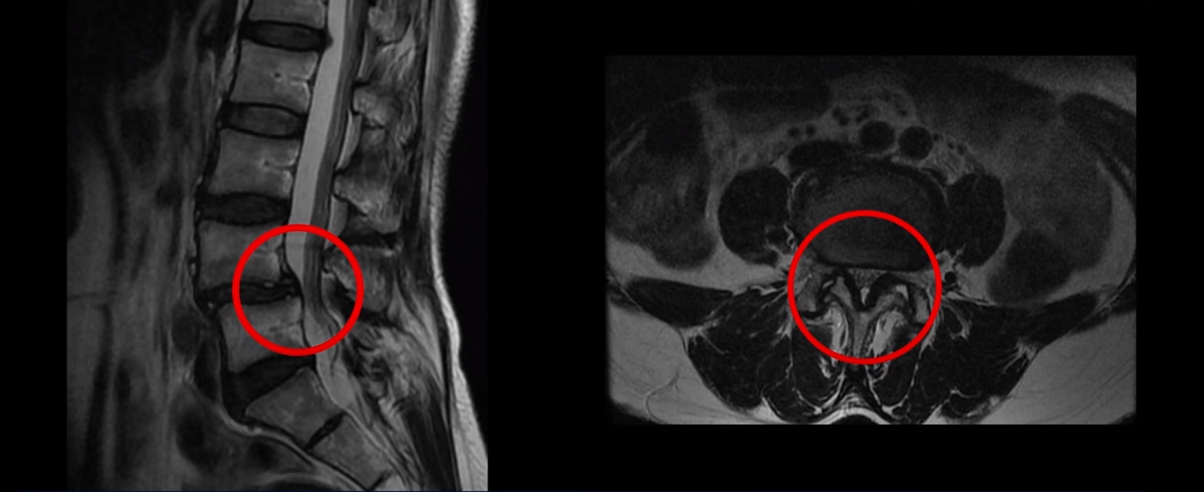

척추전방전위증을 동반한 만성허리통증으로 3년간 고생하신 환자분의 MRI 상태 및 증상은?

이 환자분은 MRI에서 보시다시피 4번 5번에 전방전위증이 있습니다. 전방전위증이 있는 분들은 디스크 문제나 협착증 문제를 동반하는 경우가 많은데 이분은 4,5번 디스크에 큰 문제는 없으시고 척추관이 약간 좁아져 있으나 다리 쪽의 증상은 전혀 없고, 오로지 만성허리통증만 있습니다. 3년 동안 허리가 심하게 아프신 상태입니다. 참고로 이분은 심하게 넘어지면서 엉덩이 근육 파열로 입원하신 상태에서 만성 허리통증 치료를 함께 받으셨습니다. 그런데 저희가 만성 허리통증이 있는데 ‘허리에 디스크가 보이든, 협착증이 보이든, 전방전위증이 보이든, 만약 다른 증상 없이 허리 통증만 있다면 그건 근육의 문제일 가능성이 매우 높다’고 여러 영상에서 설명 드렸습니다. 이분을 처음 진찰했을 때 허리 주변 근육들과 엉치 근육을 꼼꼼히 만져보았는데 역시 허리통증과 연관되어있는 중요한 근육들, 장요근, 요방형근, 기립근, 둔근이 모두 다 심하게 굳고 뭉쳐있었습니다.